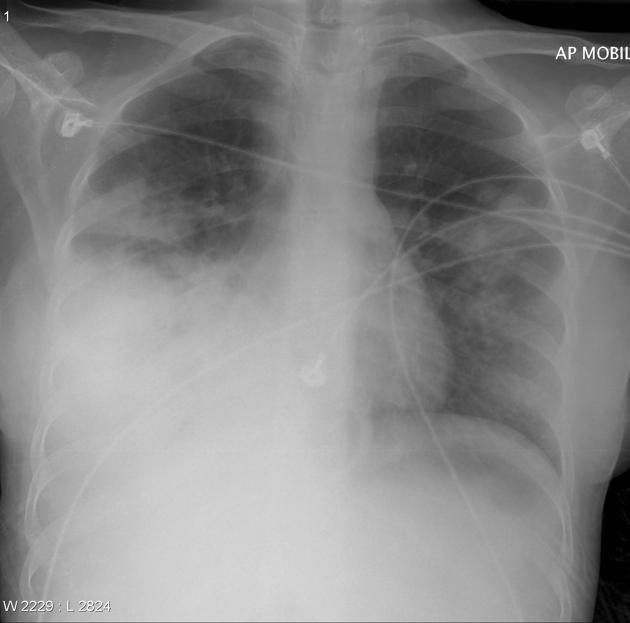

Обследование проводится в прямой и боковой проекциях грудной клетки, с прицельной съёмкой поражённых отделов лёгких, а при необходимости — в косых проекциях, в режиме обзорной рентгенографии для выявления прямых признаков пневмококковой пневмонии. Цель обследования — определение локализации, объёма и характера альвеолярного воспаления, оценка состояния лёгочного рисунка, плевры и выявление рентгенологических сигналов консолидации лёгочной ткани.

Рентгенография выявляет следующие признаки пневмококковой пневмонии:

Однородное сегментарное или долевое затемнение с чёткими внешними контурами и воздушными бронхограммами внутри, сигнализирующее об альвеолярной консолидации.

Гомогенное уплотнение лёгочной ткани, чаще в нижней или средней доле, соответствующее классическому течению крупозной пневмонии.

Сохранение или утолщение междолевых щелей на фоне воспалительных изменений, что отражает локализацию процесса.

Умеренное смещение междолевых границ и лёгкого в сторону поражения при выраженном альвеолярном уплотнении.

Реактивные плевральные изменения — утолщение плевры, локальный выпот на стороне поражения, чаще в виде пристеночного скопления жидкости.